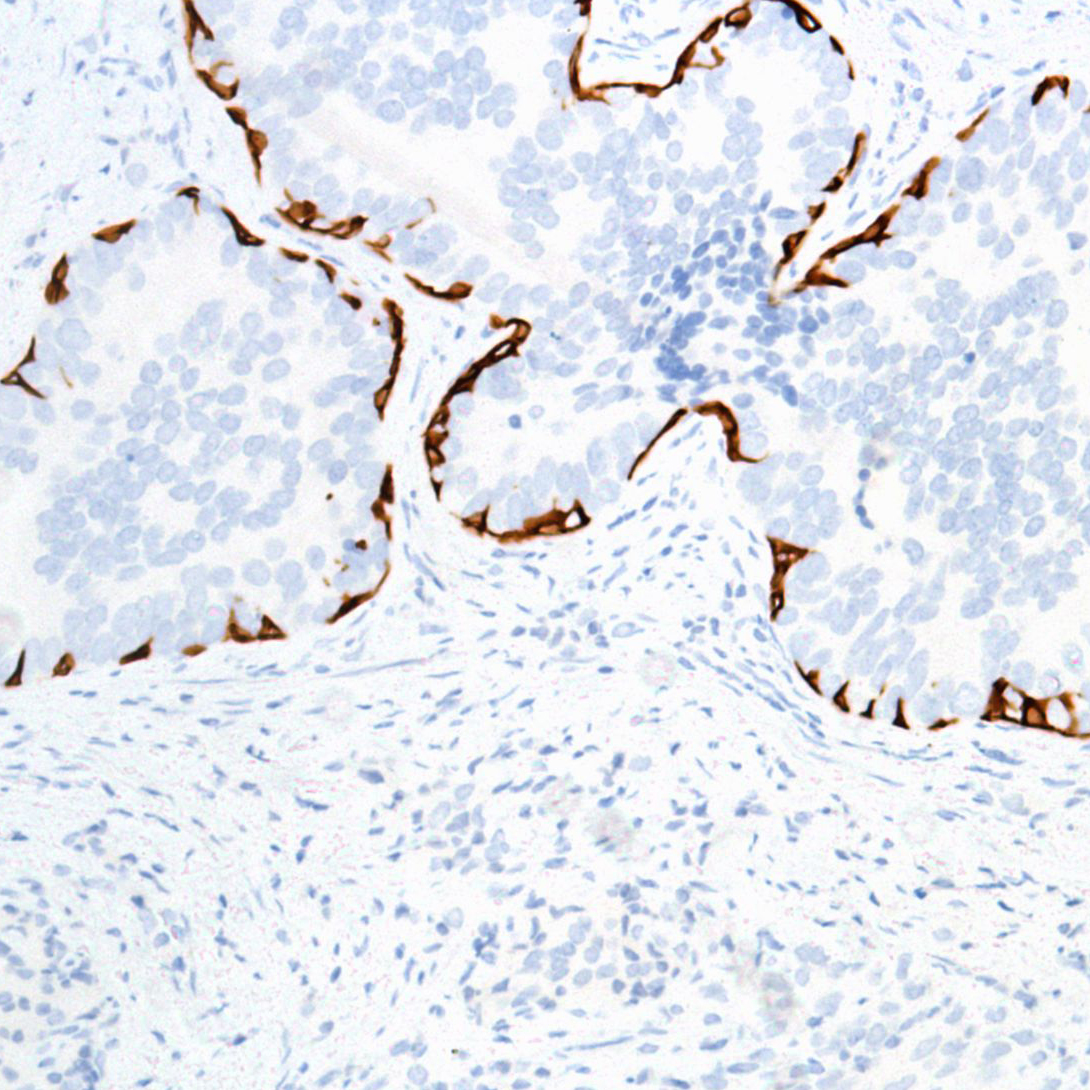

Keratin 17 (SP95)

Keratin 17 plays a role in the formation and maintenance of various skin appendages, specifically in determining shape and orientation of hair. It may be a marker of basal cell differentiation in complex epithelia and therefore indicative of a certain type of epithelial "stem cells" and also act as an autoantigen in the immunopathogenesis of psoriasis, with certain peptide regions being a major target for autoreactive T-cells and hence causing their proliferation. It is required for the correct growth of hair follicles, in particular for the persistence of the anagen (growth) state and modulates the function of TNF-alpha in the specific context of hair cycling. It regulates protein synthesis and epithelial cell growth through binding to the adapter protein SFN and by stimulating Akt/mTOR pathway and is involved in tissue repair. Keratin 17 is expressed in the outer root sheath and medulla region of hair follicle specifically from eyebrow and beard, digital pulp, nail matrix and nail bed epithelium, mucosal stratified squamous epithelia and in basal cells of oral epithelium, palmoplantar epidermis and sweat and mammary glands. It is also expressed in myoepithelium of prostate, basal layer of urinary bladder, cambial cells of sebaceous gland and in exocervix (at protein level).